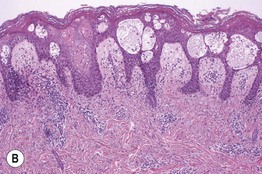

Fig. 1.9 Psoriasiform pattern. A Plaque of psoriasis vulgaris with silvery scale. B Regular epidermal hyperplasia and elongated dermal papillae with thin suprapapillary plates and confluent parakeratosis. The parakeratosis represents the histologic correlate of the visible scale. A, Courtesy, Julie V. Schaffer, MD; B, Courtesy, Carlo F. Tomasini, MD.